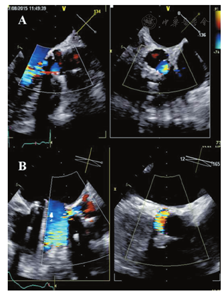

笼-球型机械性瓣膜形同鸟笼状,显示球瓣在心室侧运动。2D超声显示金属支架为强回声,而球瓣近端表面回声稍弱。动态观察,阀体在笼内前后移动。二尖瓣位置的笼-球瓣,收缩期阀体定位在缝合环内。M超声显示笼、缝合环和球瓣分别呈现4种不同的回声。单叶侧倾碟瓣表现为单一回声在心室面呈前后运动。这种瓣叶相对于瓣环的开放角度在60°~80°,导致出现大小不同的两个瓣孔。M型超声显示瓣叶开放形成多向反射的强回声。双叶PHV显示为两片独立的碟瓣,二者几乎同步开放和关闭。瓣叶相对于瓣环的开放角度在75°~90°,开放的瓣膜包括三个瓣孔:一个较小的两瓣叶间的狭缝样的中央孔和两个较大的呈半圆形的侧孔(图2)。

血流通过功能正常的PHV的血流特征不同于自体瓣膜。前向血流的特征因瓣膜位置、瓣孔的形状和数量不同而各异[7,14,83,84,85,97,98,99]。双重轮廓的多普勒频谱常见于机械性PHV中。PHV血流的多普勒频谱还包括由于阀体开启和关闭所产生的短暂、强回声、快速度的喀喇音信号(图4F,图5E)。在所有切面均应显示瓣孔被彩色血流完全充填(图2B)。

在单叶碟瓣,通常射流通过大的主孔(横截面呈半圆形射流)时产生浓密的较低速度血流,而射流通过小孔时呈暗淡的较高速度血流(依据立柱数量不同可为2~3束)。同样地,射流通过双叶机械性瓣膜的两个侧孔时产生浓密的低速血流,而通过中央孔产生暗淡的高速血流(图2F)。三股独立的射流构成前向跨瓣血流的特征性模式(图2B)。笼-球型PHV显示为血流沿整个球瓣周边通过,形成两个曲线状侧流并在中央部位形成涡流区。人工生物瓣膜前向血流模式为单一的中央性血流。